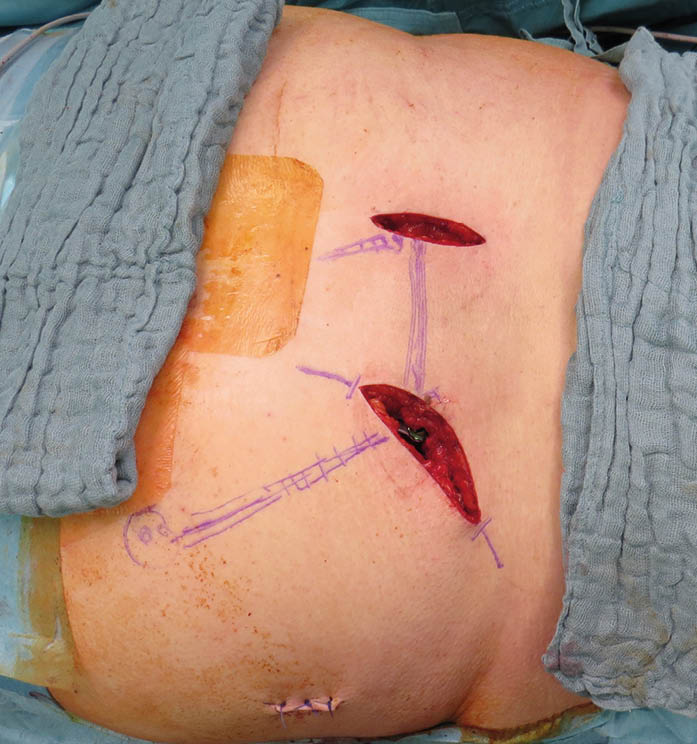

Abb. 5 (rechts) : präoperative Markierungen der Anatomie sowie orientierend der Implantatlage an Gesäß und Rücken vor/während einer monolateralen horizontalen Stabilisierung des hinteren Beckenrings rechts, rechts gluteal ist die Miniincision nach Platzierung der iliosacralen Schraube schon vernäht.

Abb. 5: präoperative Markierungen der Anatomie sowie orientierend der Implantatlage an Gesäß und Rücken vor/während einer monolateralen horizontalen Stabilisierung des hinteren Beckenrings rechts, rechts gluteal ist die Miniincision nach Platzierung der iliosacralen Schraube schon vernäht.

Aufgrund der Fixateurapplikationen erfolgt die Operation in Bauchlage, üblicherweise BV-gestützt. Es ist sinnvoll, vor der Operation lokale Anatomie und geplante Inzisionen zu markieren [Abb. 5].